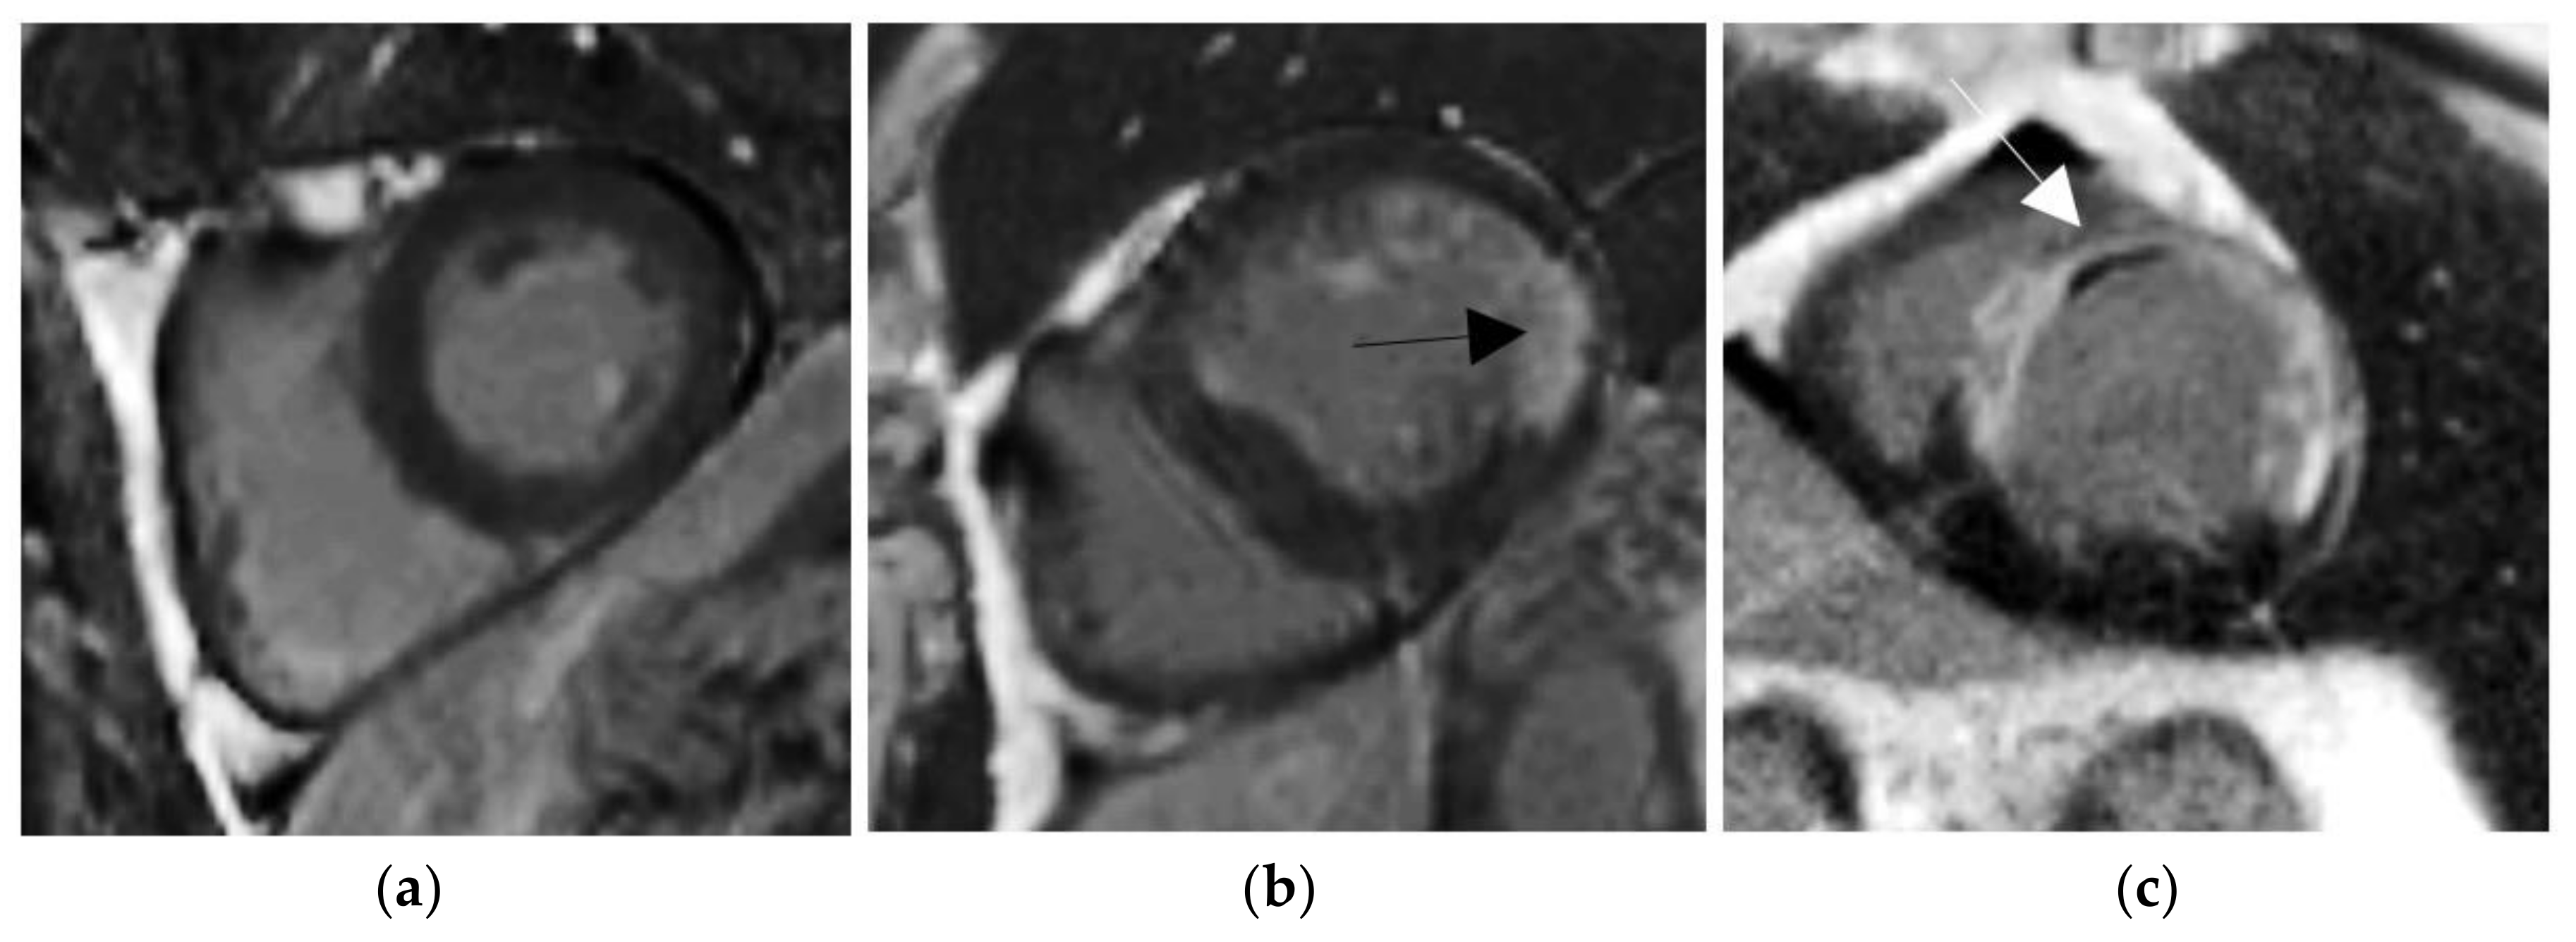

Figure 1.

Delayed enhancement (DE)-MRI examples in short axis orientation. (a) Normal myocardium. (b) Viable myocardium with a little scar (black arrow). (c) Non-viable myocardium with a transmurality scar more than 50% and the presence of microvascular obstruction (MVO) areas (white arrow).

The use of gadolinium extracellular contrast agents with MRI using late post-gadolinium myocardial enhancement sequences have further pushed our ability to accurately and precisely analyze myocardial tissue composition, especially myocardial fibrosis content [12]. In particular, the increase in gadolinium concentration within fibrotic tissue causes T1 shortening, which appears as bright signal intensity in the T1-weighted cardiac DE-MRI. The physiological basis of the gadolinium enhancement of myocardial fibrosis after several minutes is based upon the combination of an increased volume of distribution for the contrast agent and a prolonged washout related to the decreased capillary density within the myocardial fibrotic tissue [13,14]. The fibrotic area appears bright in T1-weighted MRI when the acquisition is obtained roughly 10 min after the injection of a gadolinium-based contrast agent, whereas normal tissue appears dark. We make note of the difference between early enhancement that can be studied one or two minutes after injection of the contrast agent, and the study of late enhancement, such as in our case, with acquisition roughly 10 min after the injection. The amount of contrast agent in the myocardium and the corresponding grey level on the images can be influenced by many factors, such as the renal clearance, the type of contrast media, the contrast dose, the delay between the injection of the contrast agent and the image acquisition, and the sequence parameters, among others. In our dataset, the contrast media and the sequence parameters are always the same; however, the variation of the other features involves differences in the image signal. Persistent MVO is due to persistent perfusion defect and causes irreversible damages to the intracellular zone, which finally leads to tissue death [15,16]. This latter area appears in black on T1-weighted MRI regardless of time delay between the injection of the contrast agent and the image acquisition and is always surrounded by bright area (corresponding to myocardial infarction, as shown in Figure 1c). In the presence of scar with a transmurality of 50% or in the significant presence of MVO, late gadolinium enhancement is sufficient to predict functional recovery. Fifty one percent of pathological cases have persistent MVO.